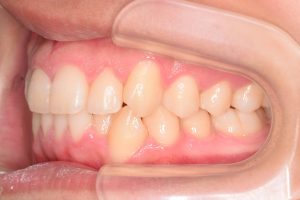

2期治療開始時(2023年7月)と装置撤去時(2025年9月)の写真です。

右側